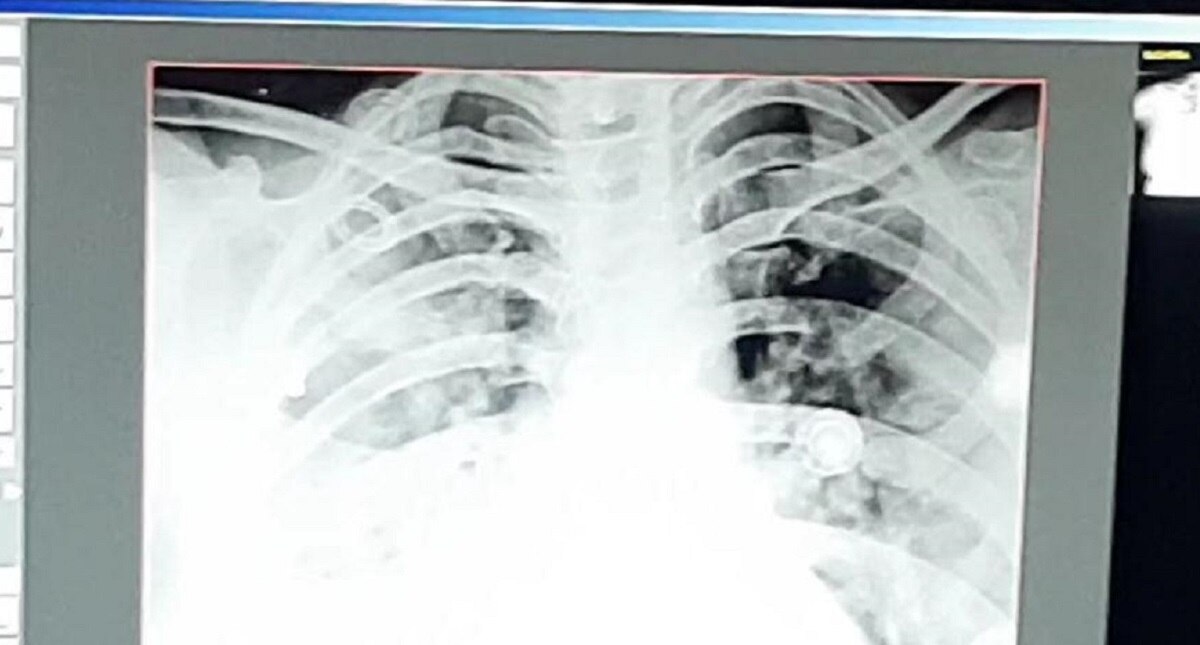

दरअसल, यह मामला कोटा का है, यहां एक 32 साल की महिला का 9 तारीख को एक्स-रे कराया तो वह ठीक थी, 12 तारीख तक भी वह महिला ठीक थी. बीपी, ऑक्सीजन लेवल, एक्स रे सब ठीक था. इसके बाद 12 तारीख की रात को घबराहट महसूस हुई.

महिला 13 तारीख को खड़ी भी नहीं हो पा रही थी, सांस लेने में दिक्कत हुई तो चेक करने के बाद पता चला कि ऑक्सीजन लेवल 94 था. 13 तारीख को सिटी स्कैन करवाया तो उसके दोनों लंग्स में 80 परसेंट तक इंफेक्शन फैल चुका था.